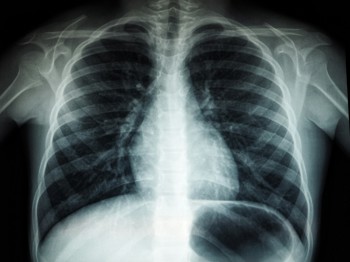

Up to £1.2m has been awarded to Cheshire and Merseyside to accelerate the implementation of an AI imaging and support tool which can analyse chest X-ray images and identify possible signs of lung cancer.

The tool, which will be rolled out to nine acute and specialist NHS trusts across Cheshire and Merseyside, can identify nodules and masses on chest X-rays to both ensure those patients can be prioritised and reduce the administrative burden on clinical staff.